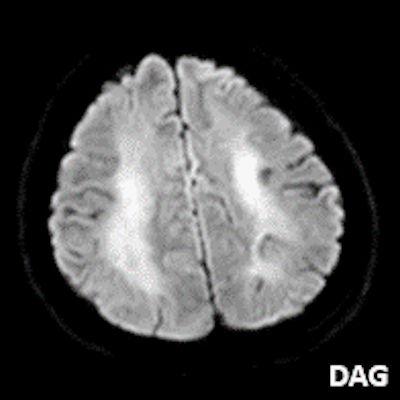

- A) Bilateral serebral kortekste (oklar) ve bazal ganglionlarda (oklar) yaygın DAG hiperintens, ADC hipointens difüzyon kısıtlamaları görülüyor.

- DAG görüntülemede sıklıkla belirgin difüzyon kısıtlaması görülür.